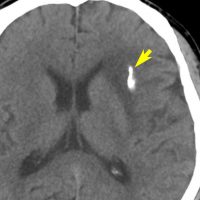

診断 CT

• CTでは,石灰化やのう胞を伴う境界不鮮明な低吸収域(黒っぽく見える)として捉えられます

• 特に石灰化は星細胞系腫瘍との鑑別診断に非常に重要な所見です

• 脳石 brain stoneといわれる岩のような大きな塊の石灰化もあります

CTで白く見えるのが石灰化です。周りの少し黒っぽいところは乏突起膠腫です。CTでは腫瘍の全体像は見れませんからMRIが必要です。